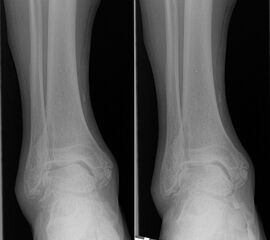

Native Röntgenaufnahmen des Sprunggelenks in 2 Ebenen unter Belastung (antero-posterior und lateral) erlauben Gelenkspaltverschmälerung, osteophytäre Anbauten sowie Achsfehlstellungen zu beurteilen. Eine „Canale-Aufnahme“ (Pronation des Fußes von ca. 15 °, Röntgenstrahl 75 ° nach kranial) 9 kann hilfreich sein, die subchondralen Oberflächen einzusehen. Die korrekte Abbildung der Sprunggelenkgabel in der sogenannten „Gabel-Aufnahme“ (mortise-view) ist zudem notwendig zur Beurteilung der Gelenkkongruenz. An Grenzen stößt die konventionelle Röntgenaufnahme allerdings bei OCLs ohne weitere knöcherne Veränderungen. Bis zu 50% der OCLs sind auf konventionellen Röntgenaufnahmen nicht sichtbar. Auch kann der Zustand des Knorpels nicht beurteilt werden 10. Bei Achsfehlstellungen werden zusätzlich Rückfußachs-Aufnahmen (Saltzman View) angefertigt bzw. eine Einbeinstandaufnahme zur Bestimmung der Becken-Bein-Achse.

Zur Vollansicht und zum Lesen der Bildbeschreibung bitte das Bild anklicken.